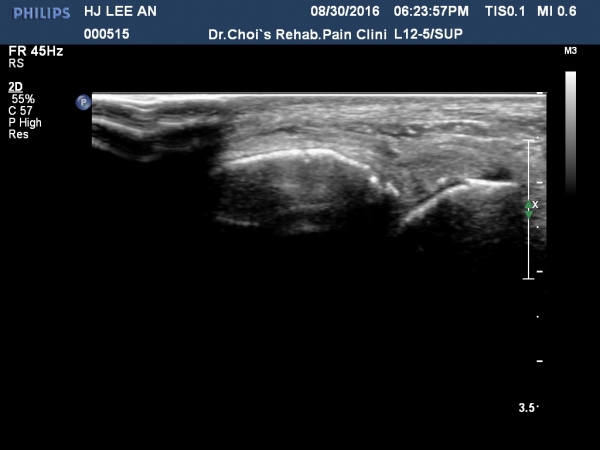

Àü°ÅºñÀδë Á¾´Ü¸é°Ë»ç¿¡¼­ ÀδëÀÇ Àú¿¡ÄÚ ºÎÁ¾ÀÌ °üÂûµÇ³ª °ß¿­°ñÀýÀº °üÂûµÇÁö ¾ÊÀ½(»çÁø 4, 5, 6, 7)

Àü°ÅºñÀδë ÃÊÀ½ÆÄÀ¯µµÇÏ ºÎÇϰ˻翡¼­ ÀδëÀÇ ºñ°ñºÎÂøºÎ¿¡¼­ Àδë¿Í ºÎÂøµÈ °ñÆíÀÇ ÀÌÅ»ÀÌ

°üÂûµÊ(÷ºÎµ¿¿µ»ó).